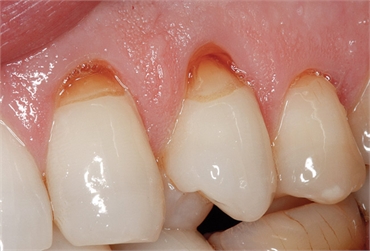

Teeth abrasion is a dental condition that involves the disintegration and loss of tooth structures usually caused by external forces such as toothbrushes and toothpicks. This condition starts by attacking the typically strong outer cover part of the tooth known as the enamel. Once past the enamel, tooth abrasion quickly destroys the much softer dentin and cementum tooth structures. This stretches onto the teeth roots, dismantling the roots and teeth gums holding your teeth. Since the enamel is usually tough to disintegrate, this condition usually starts from a weak-point enamel part of the tooth that is known as the cemento-enamel junction (CEJ). This junction is usually thinner than the other parts of the outer tooth cover thus allowing for quick erosion of its structure.

Tooth abrasion can also cause your gums to recede and therefore lose the much needed grip that is important for healthy teeth. Your facial look can be affected greatly since the premolars and canines turn out to be the most affected teeth by this dental condition. This might affect your confidence in smiling and speech. The condition is known to cause severe sensitivity or even pain if left untreated.